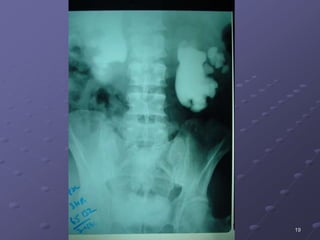

Investigations

i.v.u

19

20